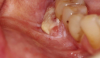

Ill fitting dental appliances such as partials and dentures irritate the gingiva and trap debris. Continued irritation can lead to lesions and eventually develop into oral cancer (Figure 2).